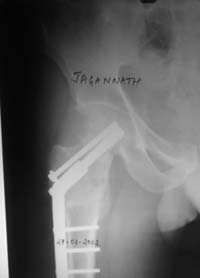

Stephen Kottmeier 17 Октябрь 2005, 21:05

friend

dhs will not correct improper biomechanical environment and may further compromise vascular

integrity consider establish vascular status via mri

and if viable follow with proximal valgus osteotomy

case provided s/p failed fixation

Отправитель: Peter Trafton 17 Октябрь 2005, 21:21

I think that this 31 yo deserves a try with valgus osteotomy, as so nicely illustrated by stephen kottmeier. However, I'd do it no matter what an MRI shows - thus why bother with the MRI? (What sort of data support MRI's ability to predict segmental collapse?)